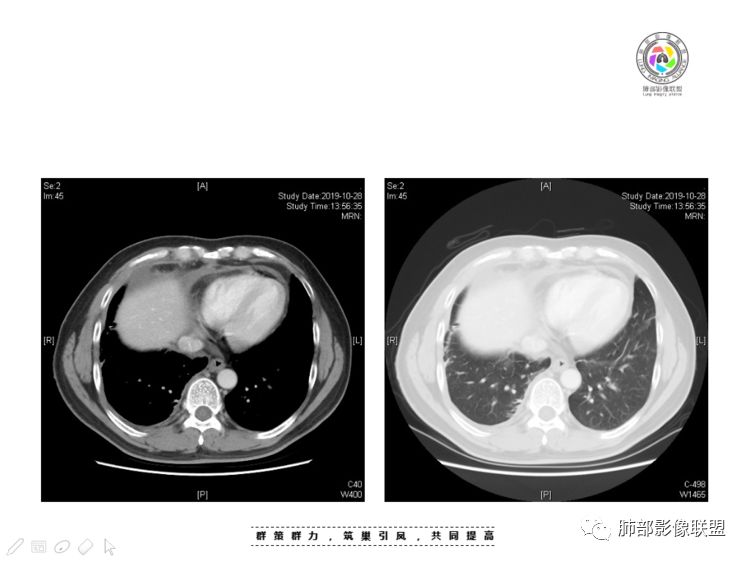

肺内结节,近端支气管堵塞狭窄

整体边缘收缩,部分膨隆

炎性要考虑,但恶性不能排除

1、右肺内病灶,病灶呈结节样,边缘欠规则,局部膨隆,叶间裂胸膜牵拉凹陷,再看相应支气管腔堵塞截断,临床资料胸水中查到癌细胞,均提示病灶倾向恶性,腺癌的病理意见与之相吻合。

黄勇老师总结,腺癌如果与胸膜、叶间裂紧贴或伴胸膜凹陷,胸膜、叶间裂多发结节,应当高度怀疑腺癌转移。

胸腺瘤/胸腺癌:病灶内那么大的囊,常规考虑B型以上胸腺瘤,囊内有分隔影,病灶周围脂肪间隙模糊,常规考虑侵袭性胸腺瘤或胸腺癌,若侵袭性胸腺瘤,常侵犯胸膜、心包,很少累及肺。胸腺癌易侵犯胸膜、肺并纵隔淋巴结及远处转移。但肺内腺癌形态更符合原发灶。胸膜及叶间裂转移则即可来自肺,也可来自胸腺癌。